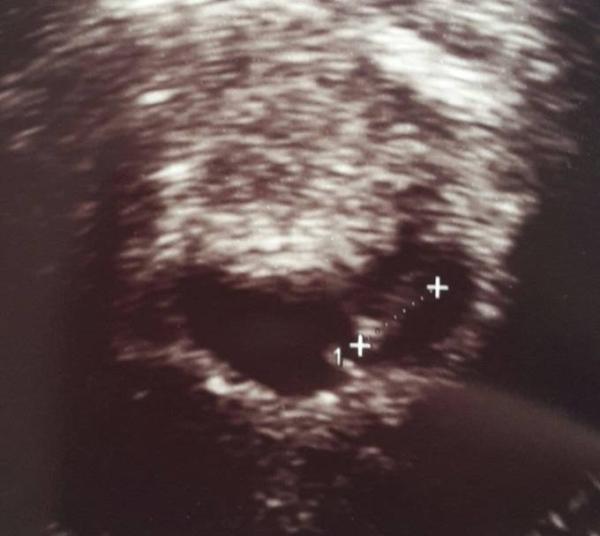

Hey ihr Lieben, Bin gerade vom ersten FA Besuch zurück. Die Ärztin kuckt und meint: "ich sehe eine fruchthöhle, aber da ist nix drin." Mir ist das Herz in die Hose gerutscht. .. Dann hat sie weiter "gewühlt" und dann endlich: "Ah da ist doch was." Hatte sich in die Ecke gedrückt Hat dann auch den Herzschlag gefunden . Ich bin sooo happy . Auf dem Bild kann ich nicht so viel sehen vielleicht erkennt ihr mehr... bin jetzt rechnerisch bei 6+5. LG P.S. Ergebnis der "brust-knubbel" Untersuchung schreibe ich euch direkt unter den Beitrag von MommyChaos von heute morgen.

Bild zu Jetzt offiziell im Januarbus - Forum für Januar - Mamis